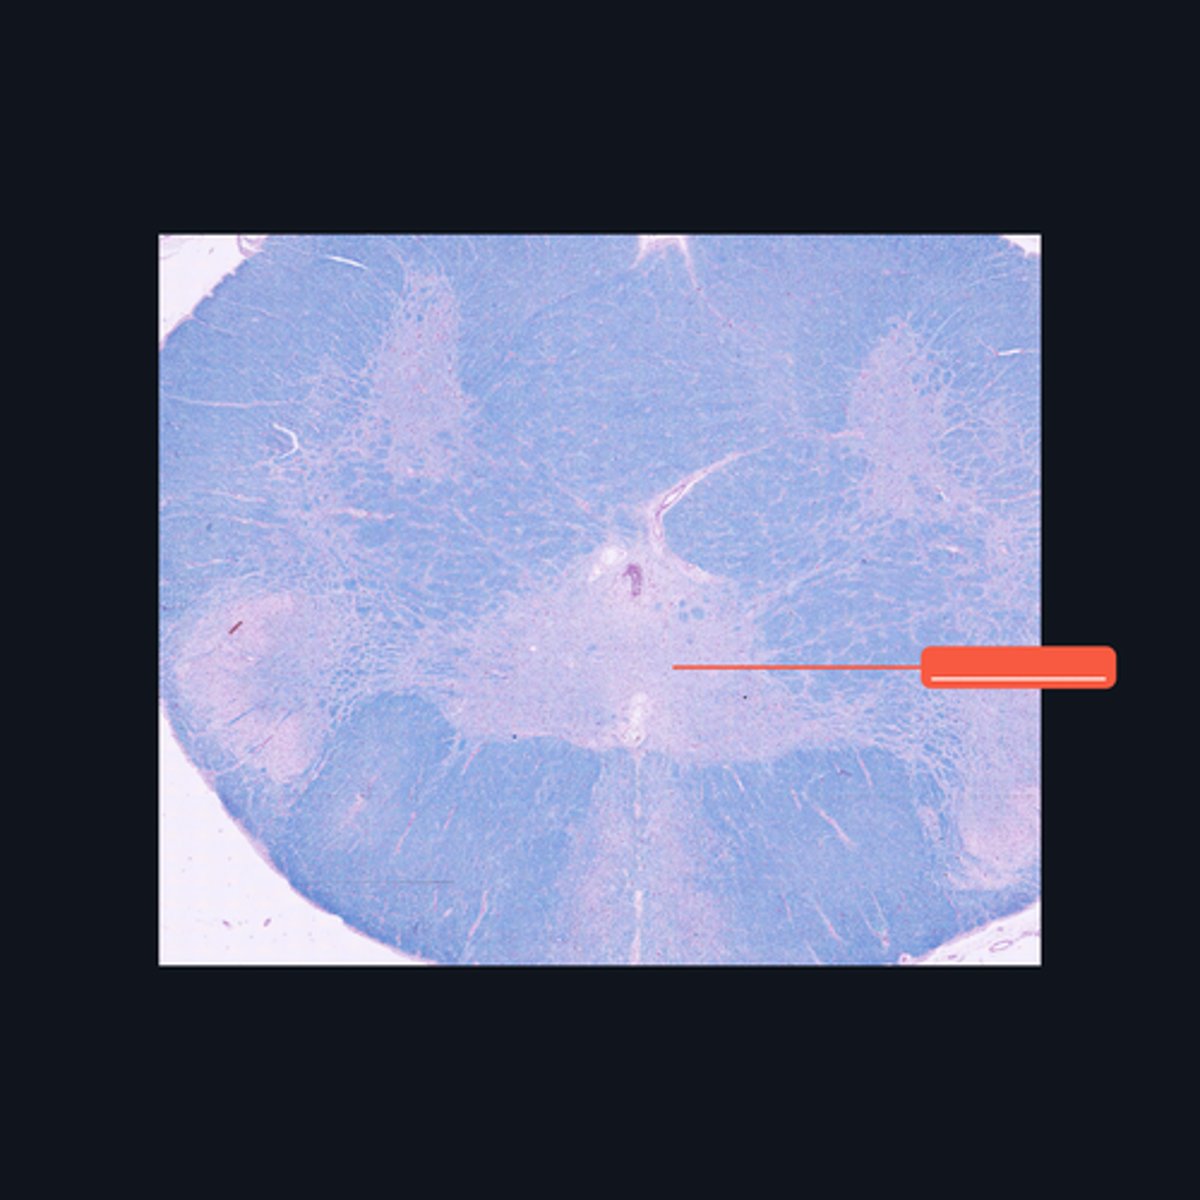

Choroid Plexus

Identify the region of the brain in the given image.